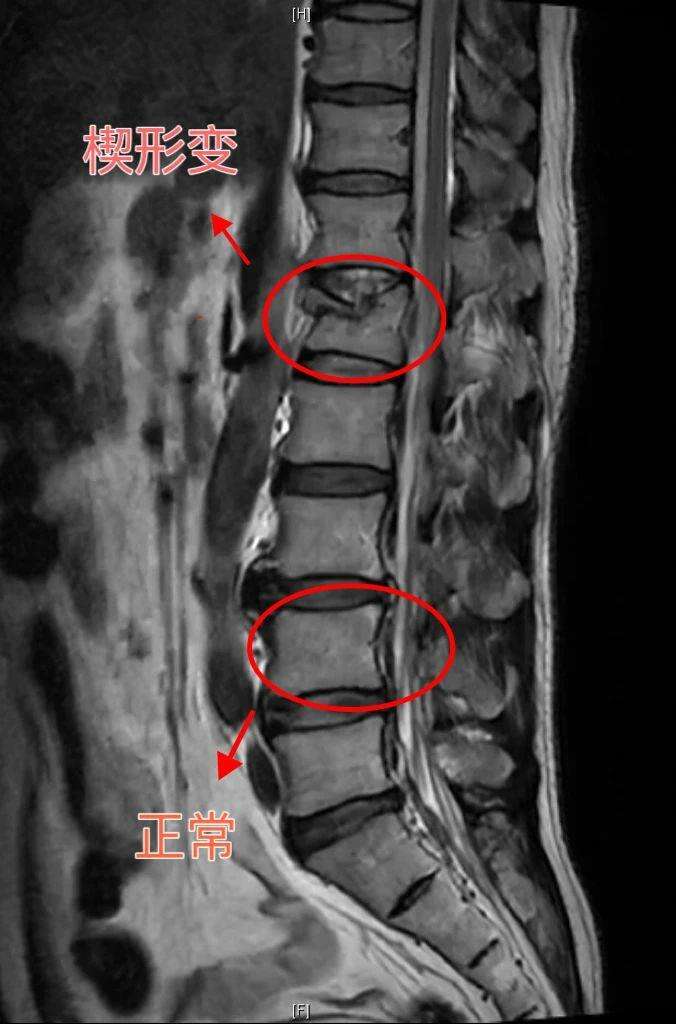

有人会说,太夸张了吧!打个喷嚏咳嗽一声能骨折?是不是危言耸听啊!还真不是。如果给脊柱骨拍张照片啊,这腰椎一块块码起来,每块都长得是一个四四方方的长方形。本来腰椎应该是每块骨头都特结实,一块连着一块,码得整整齐齐。但是由于重度骨质疏松,腰椎力气不够了,顶不住了,从长方形压缩变成了一个楔子的形状,这就是所谓的“楔形变”。也就是说小方块前端压缩了,压缩了以后呈一个楔子样,变得前窄后宽了。这种情况,在医院的放射科报告的上,就叫作“腰椎楔形变”。

慢性椎体压缩性骨折有一个特点:不易发现。为什么呢?因为腰椎骨折不像其他的胳膊腿儿折了,症状特别明显,疼啊,肿啊,动不了啊,那一看就是骨折了。轻度的腰椎骨折,这人还能坐起来,还能弯腰,从后背都看不出来有什么变化。所以特别容易被以为是常见的腰疼:“最近老是腰疼”“腰疼的老毛病又犯了”。重度的腰椎骨折,也就是说楔形变程度重的话,严重的前边窄后边宽,就会形成驼背。您想啊,本来是一块块的四四方方整整齐齐的小方块,现在好几块都变形了,变得前边窄后边宽,那脊柱整个就弯曲了。所以多节楔形变,就是多节椎体压缩性骨折。